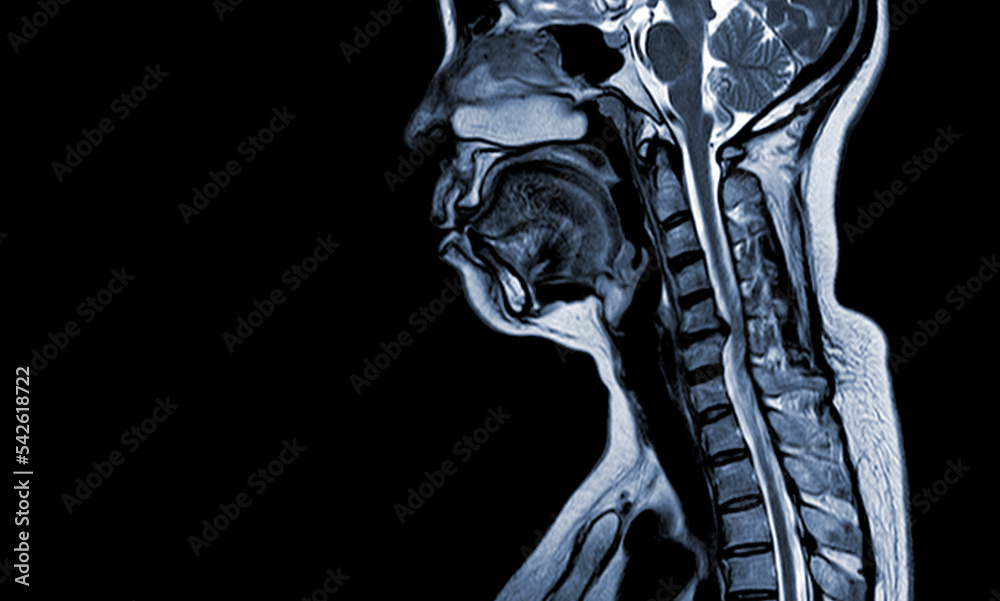

Cervical cord compression on MRI. (A) T1 and (B) T2weighted sagittal Cord Compression Mri Protocol Use of a compartmental spinal mri approach in patients with suspected nontraumatic spinal. The field is centred on the cord compression, including 1 vertebra above and below. Spinal cord compression (scc) is a surgical emergency, usually requiring prompt surgical decompression to prevent permanent. Attention to the transverse axial imaging is important to. Traumatic cord compression is treated by removal of. Cord Compression Mri Protocol.